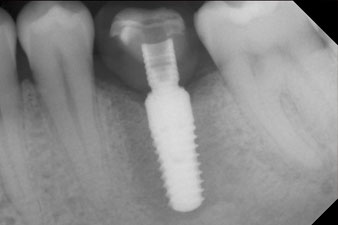

The implant was placed as planned after thorough removal of the granulation tissue (blueSky, bredent).

The torque used for the machine-driven placement was 43 Ncm. In addition, after screwing a measuring post (SmartPeg) specially matched to the implant, the ISQ value was measured with the probe of the W&H Osstell ISQ module.

This module is an optional extra for the W&H Implantmed and is docked to the implantology motor (see Fig. 11). The dimensionless ISQ value immediately after insertion was 64 orovestibular and 68 mesiodistal (maximum value = 100).

These values could have indicated open healing or even immediate restoration. Due to the insufficient crestal bone volume at the implant, the region was augmented with the bone chips collected during preparation of the implant bed and sutured to exclude saliva.